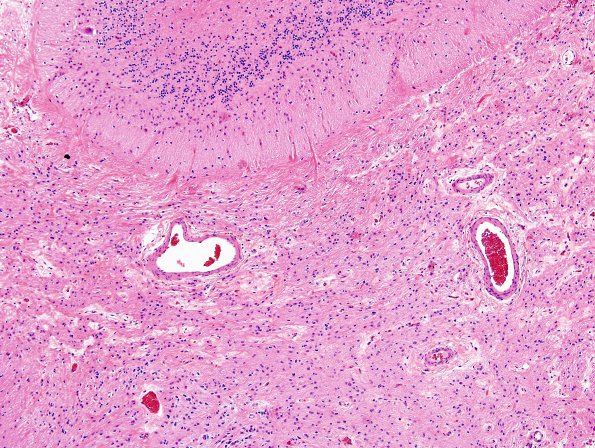

2B4 Astrocytoma, pilocytic (Case 2) H&E 10X

Invasion of the subarachnoid space by tumor (H&E)